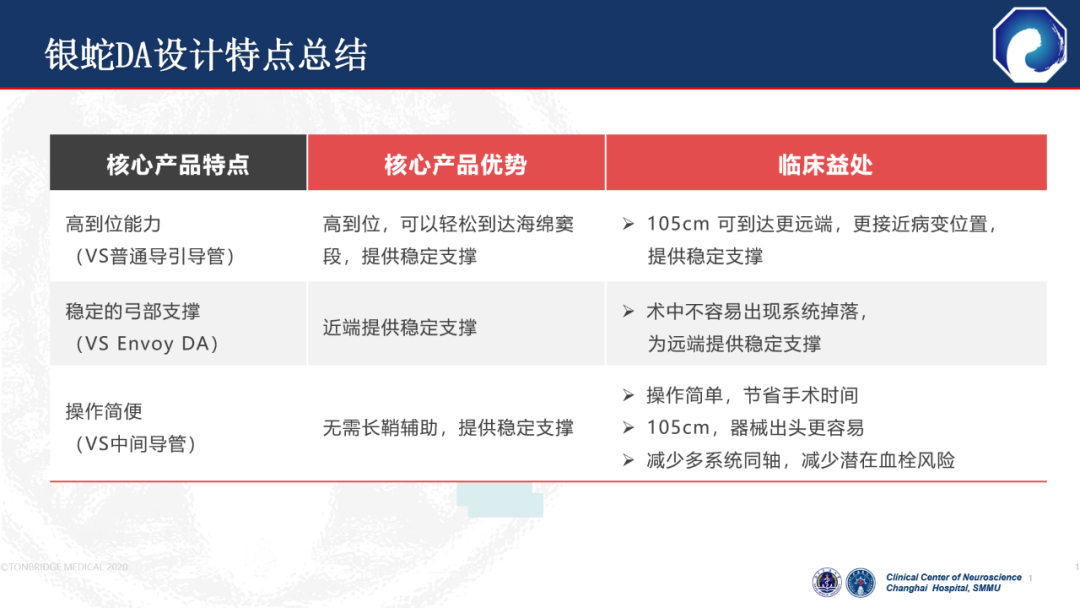

7种材料的组合带来了更优的通过性与近端支撑力

与竞品DA相比,弓部和近端支撑力更强

40°头端预塑形,主动脉弓超选更容易。0.071大内腔设计,可以兼容多种器械

105cm长度设计,器械出头更容易

通桥医疗银蛇®DA在迂曲血管中也能实现高到位

通桥医疗银蛇®DA设计特点